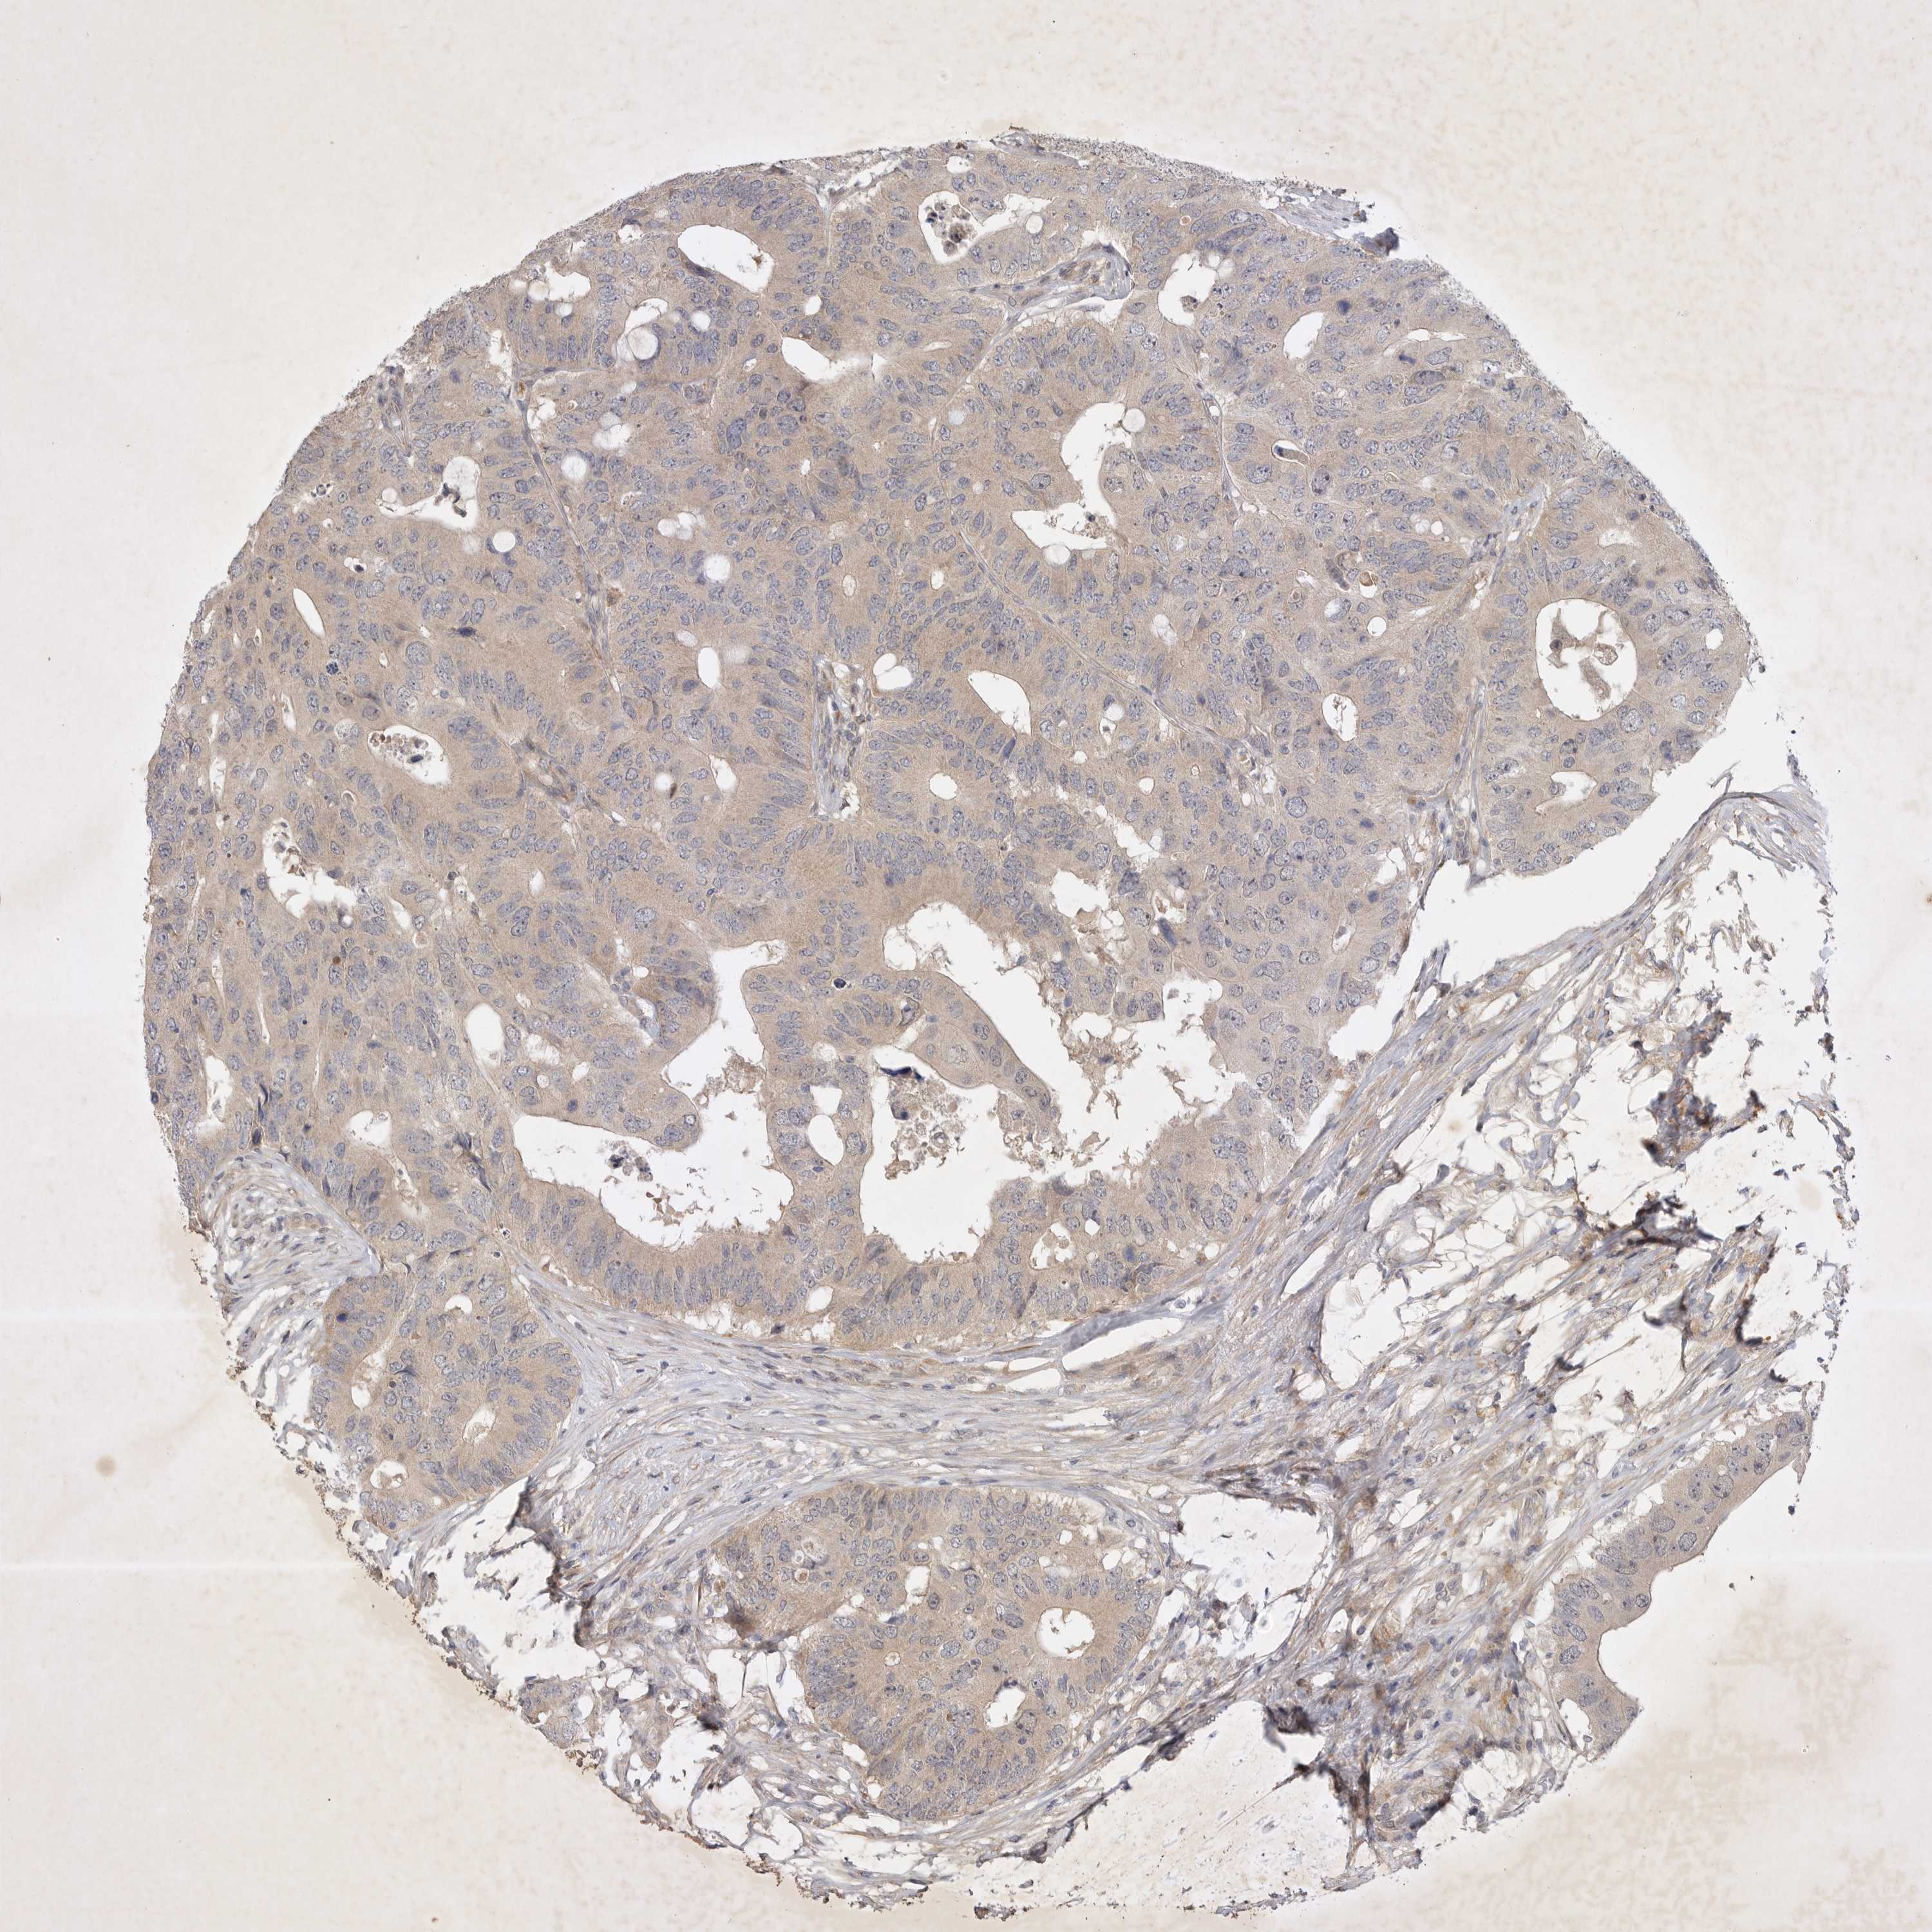

CANCER COLORECTAL CANCER Show tissue menu

Colorectal cancer

Colon adenocarcinoma